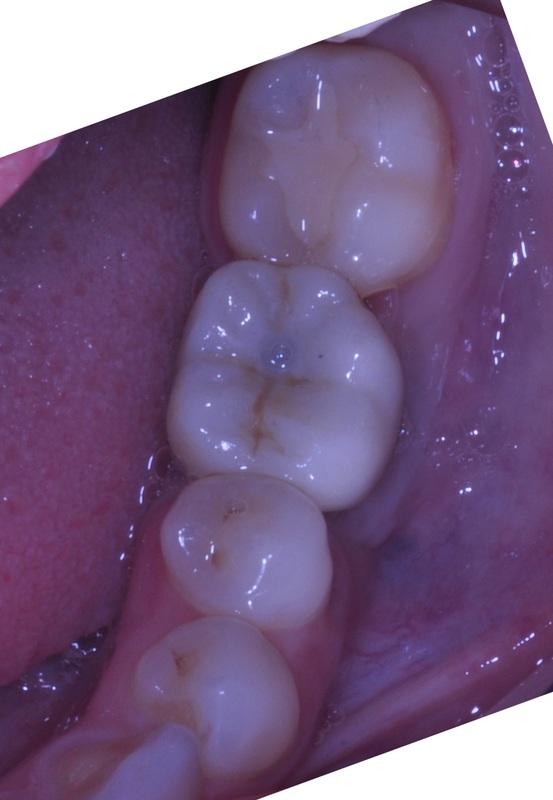

SEVERAL TEETH REPLACEMENT

This 65 year old man had pain in his lower jaw, during initial emergency exam after recent extraction of the lower left molar done with another dentist.

The patient suffers from Type 2 insulin-dependent diabetes. For unknown reason, the extraction site had not been closed with sutures by his previous dentist. On the second day after extraction, a “dry socket” had developed. This infection had caused moderate loss of bone due to the inflammatory process.

The treatment performed by Dr, Andrews included :

- Management of the dry socket.

- Simultaneous placement of three dental implants, combined with bone graft.

- PRF protocol was also used, in order to decrease the likelihood of complications (infection, bleeding), to accelerate the healing process and to decrease post-operative discomfort.

All three implants were successfully integrated and restored 6 months after the surgery.